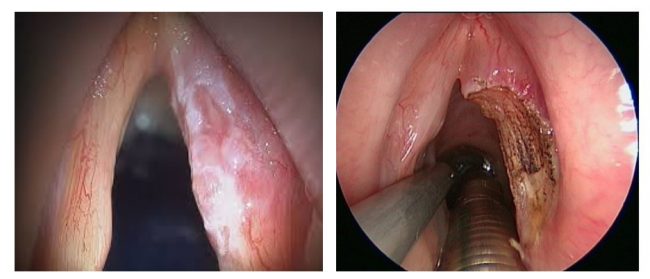

Структуры пазух носа, также называемые придаточными пазухами носа, представляют собой 4 пары воздушных пространств, расположенных внутри лицевых костей, и каждая названа в честь костных структур, в которых они расположены (верхнечелюстная, решётчатая, лобная и клиновидная пазухи). Пазухи, которые частично присутствуют при рождении, почти полностью развиваются примерно к 12-14 годам. Он имеет такие функции, как увлажнение вдыхаемого…